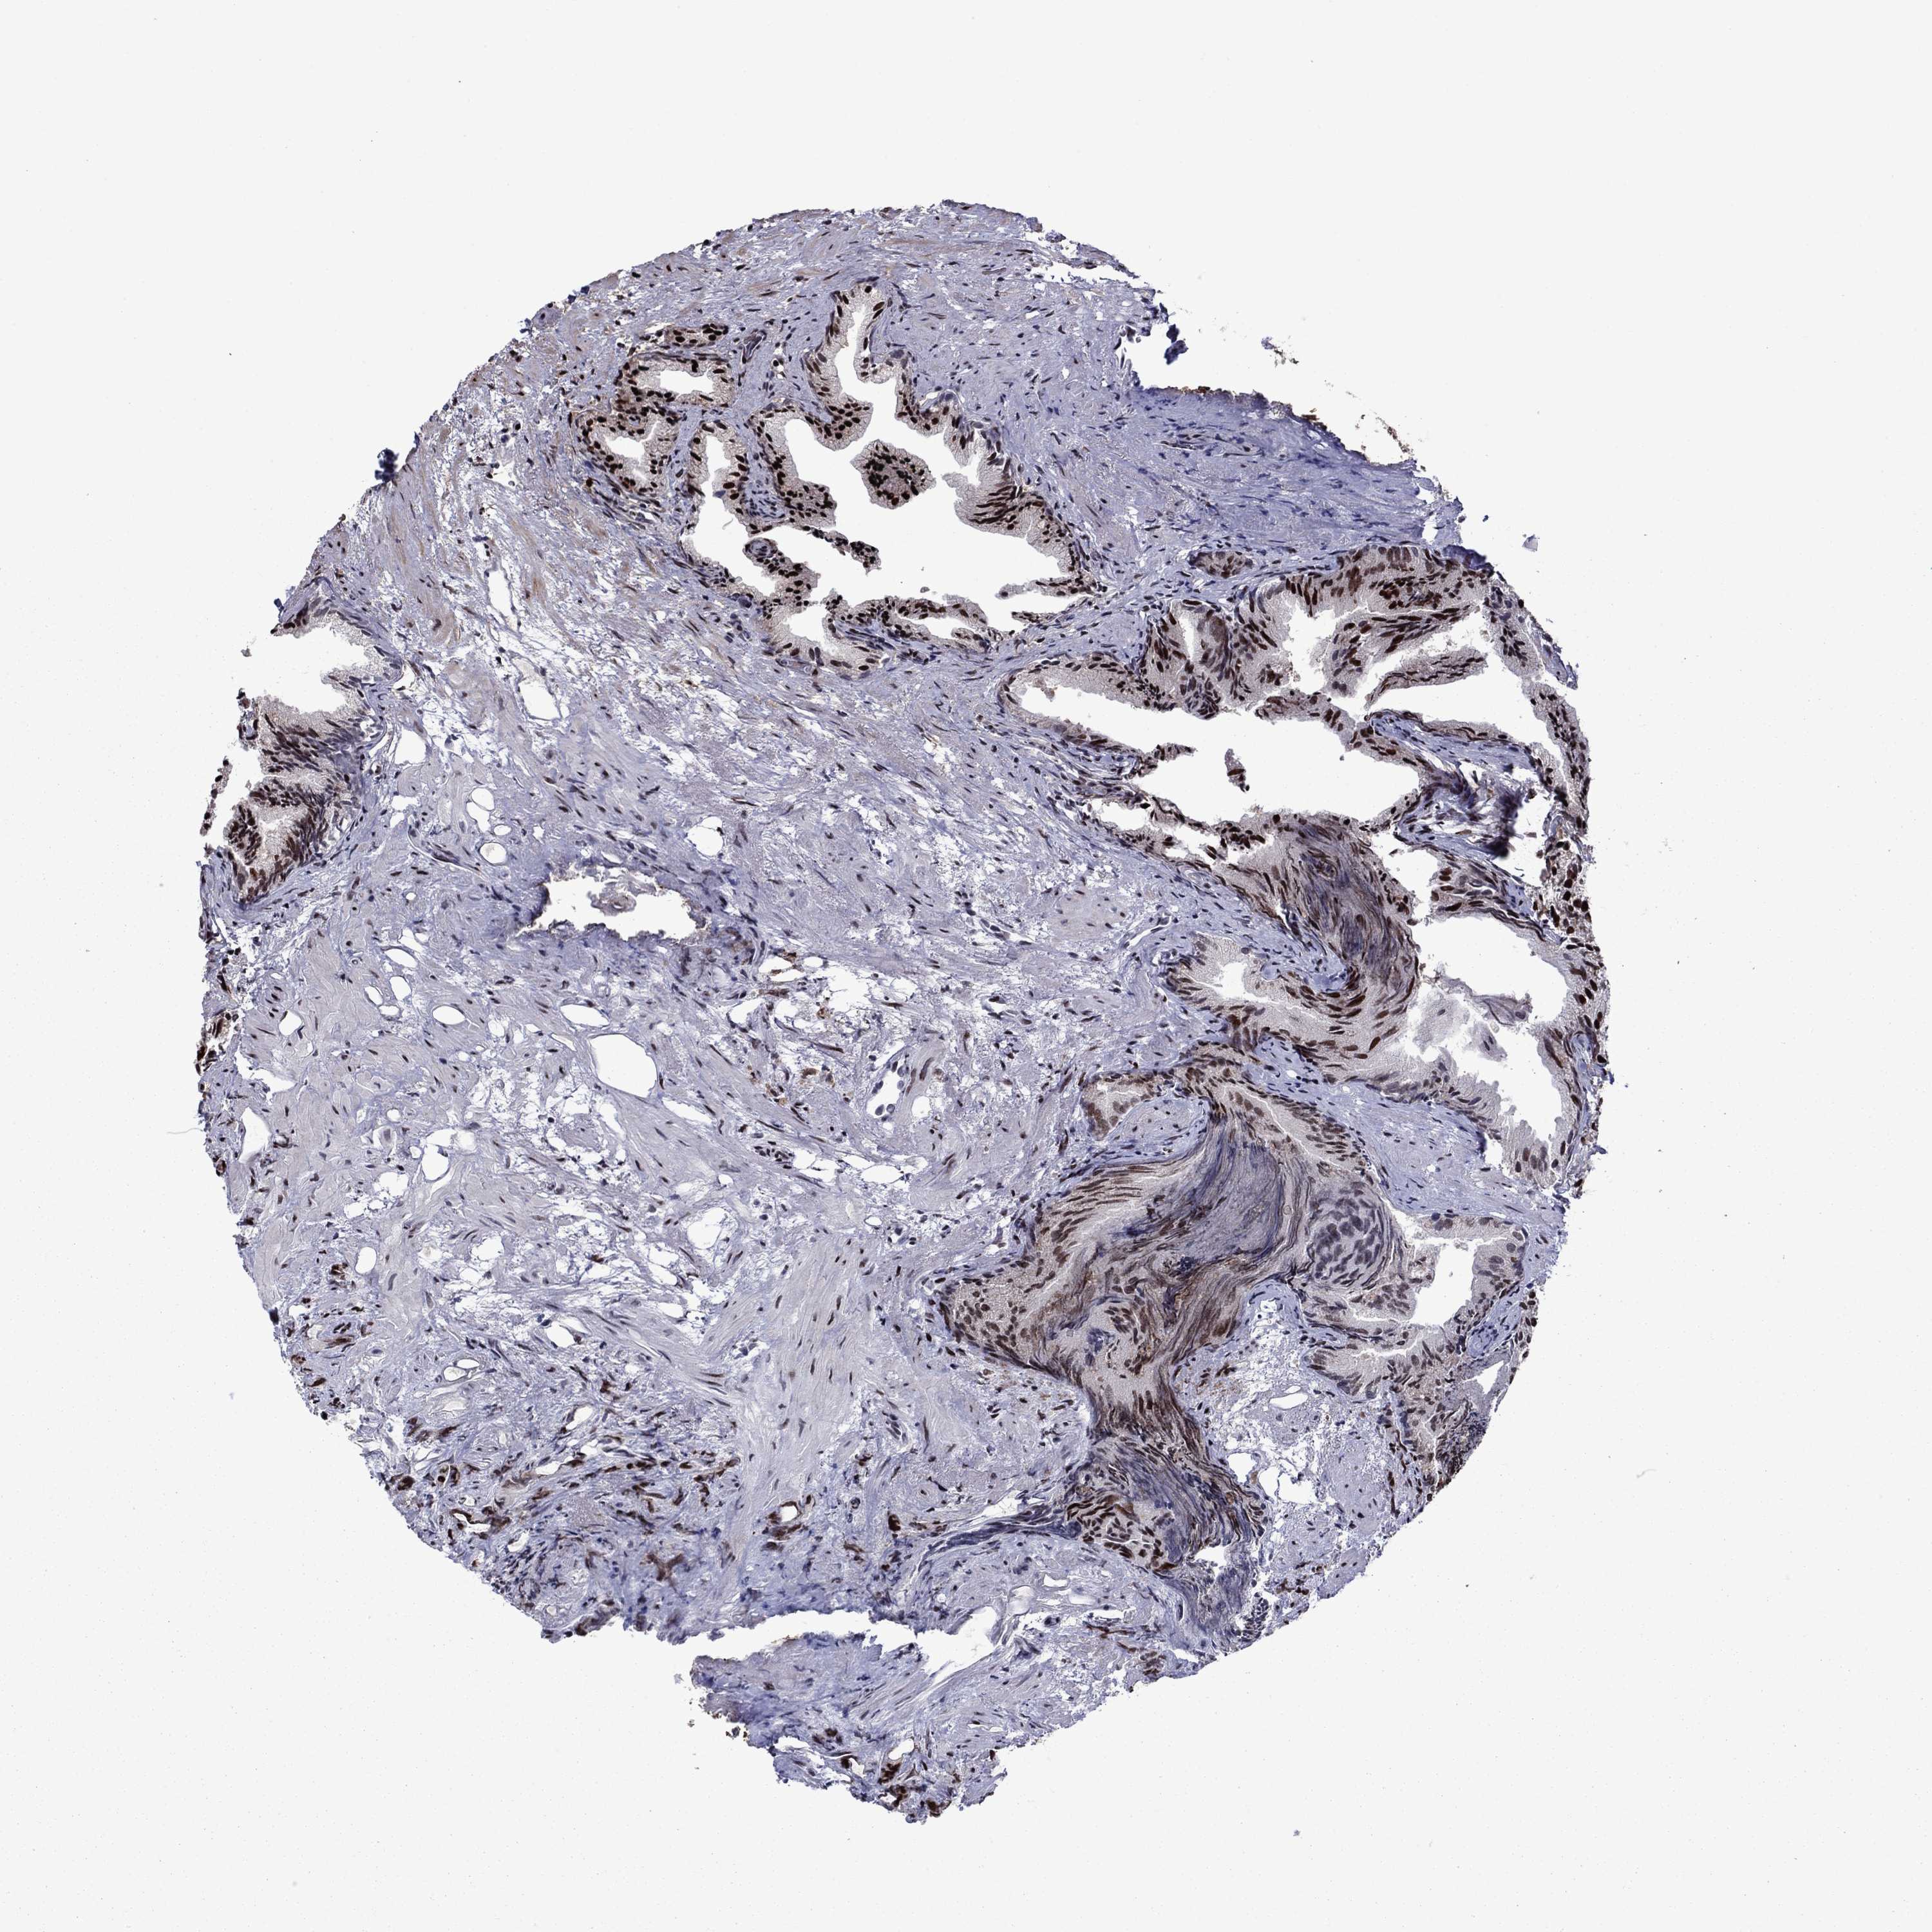

PROSTATE CANCER - Protein expressioni

A mouse-over function shows sample information and annotation data. Click on an image to view it in a full screen mode. Samples can be filtered based on level of antibody staining by selecting one or several of the following categories: high, medium, low and not detected. The assay and annotation is described here.

Antibody stainingi

Antibody staining in the annotated cell types in the current human tissue is reported as not detected, low, medium, or high, based on conventional immunohistochemistry profiling in selected tissues. This score is based on the combination of the staining intensity and fraction of stained cells.

Each image is clickable and will lead to virtual microscopy that enables deeper exploration of all samples and also displays staining intensity scores, fraction scores and subcellular localization as well as patient and tissue information for each sample.

Antibody HPA028516

Antibody HPA073571

Staining

High

Medium

Low

Not detected

Intensity

Strong

Moderate

Weak

Negative

Quantity

>75%

75%-25%

<25%

None

Location

Nuclear

Cytoplasmic/membranous

Cytoplasmic/membranous,nuclear

Adenocarcinoma, High grade

Adenocarcinoma, Low grade

Adenocarcinoma, Medium grade

Adenocarcinoma, NOS